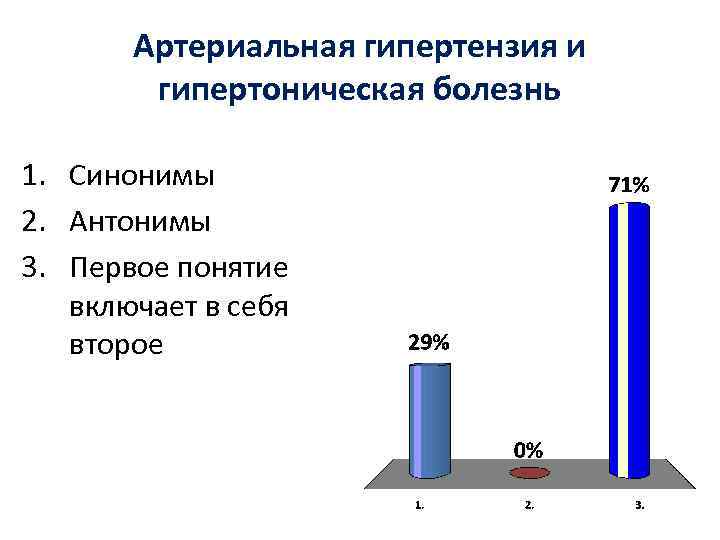

Артериальная гипертензия и гипертоническая болезнь 1. Синонимы 2. Антонимы 3. Первое понятие включает в себя второе

Артериальная гипертензия и гипертоническая болезнь 1. Синонимы 2. Антонимы 3. Первое понятие включает в себя второе

Артериальная гипертензия (АГ) симптом синдром повышения АД при гипертонической болезни и симптоматических АГ Термин “гипертоническая болезнь”, предложенный Г. Ф. Лангом в 1948 г. , соответствует употребляемому в других странах понятию “эссенциальная гипертензия”. Под гипертонической болезнью принято понимать хронически протекающее заболевание, основным проявлением которого является АГ, не связанная с наличием патологических процессов, при которых повышение АД обусловлено известными, в современных условиях часто устраняемыми, причинами (симптоматические АГ).

Артериальная гипертензия (АГ) симптом синдром повышения АД при гипертонической болезни и симптоматических АГ Термин “гипертоническая болезнь”, предложенный Г. Ф. Лангом в 1948 г. , соответствует употребляемому в других странах понятию “эссенциальная гипертензия”. Под гипертонической болезнью принято понимать хронически протекающее заболевание, основным проявлением которого является АГ, не связанная с наличием патологических процессов, при которых повышение АД обусловлено известными, в современных условиях часто устраняемыми, причинами (симптоматические АГ).